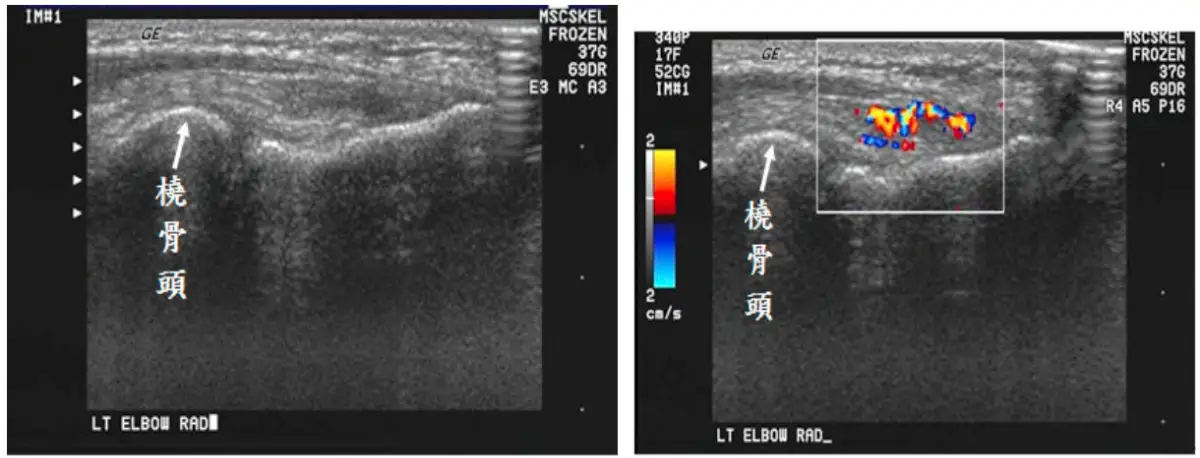

49歲男性病人,主訴左肘關節疼痛,尤其在橈側( radial side ),灰階及彩色杜卜勒超音波檢查如圖,最可能診斷為何?

本題探討 lateral epicondylitis(網球肘)在超音波下的典型表現,包括 common extensor tendon 的結構改變與 neovascularization。

從灰階(B-mode)影像可見於橈骨外側髁(radial head)附著處,common extensor tendon(共同伸肌腱)明顯增厚,迴聲降低且呈現不均質,有區域性的低回聲或缺損(hypoechoic defects),暗示腱纖維變性或微撕裂。在彩色 Doppler 圖像中,病灶區域血流訊號明顯增多,顯示活化的血管新生(neovascularization)與慢性發炎反應。此影像特徵與 lateral epicondylitis 的超音波所見相符,因該病常因 extensor carpi radialis brevis 過度負荷引發腱病變並伴隨微血管增生。